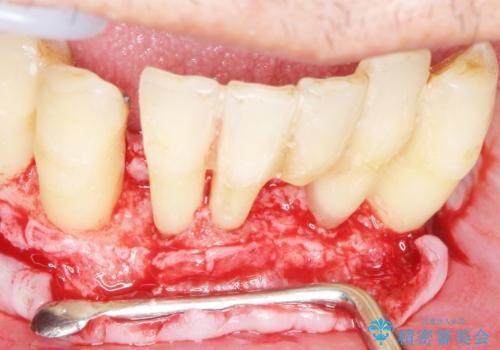

精査したところ、全顎的な重度の歯周病により下顎前歯に激しい動揺を認めました。

できるだけ自分の歯を残したいという患者様の強いご希望により、禁煙指導後再生療法(骨を増やす手術))を行いました。

再生療法から1年後リエントリー手術により骨の再生を確認し、骨外科処置(骨を平らにして歯周ポケットの根本的な改善を図る処置)を行ったのち、連結補綴を行いました。

骨吸収と動揺が著しい前歯1本(左下1)のみ抜歯しております。